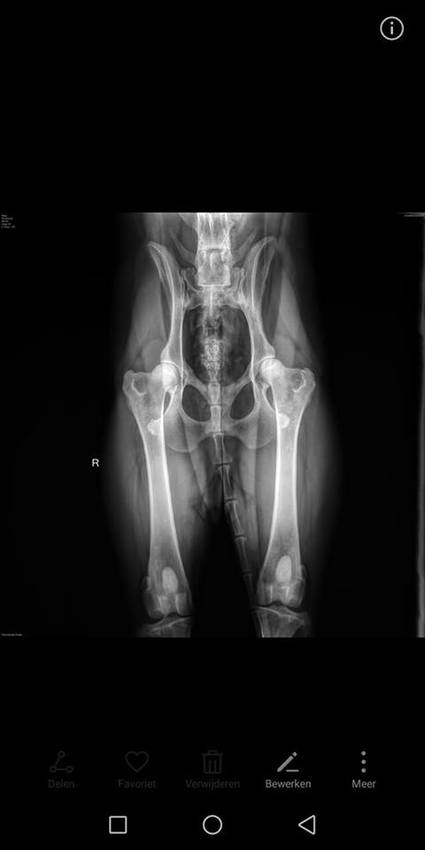

Intussen zijn we natuurlijk allang geweest, maar ben vergeten een update te plaatsen!

Abby heeft HD A, is ED vrij en ook Patella Luxatie is ze vrij van!

Haar rug waren ook geen bijzonderheden te zien.

De dierenarts was zeer tevreden en vond haar ook een zeer geschikte kandidaat voor de fok :)